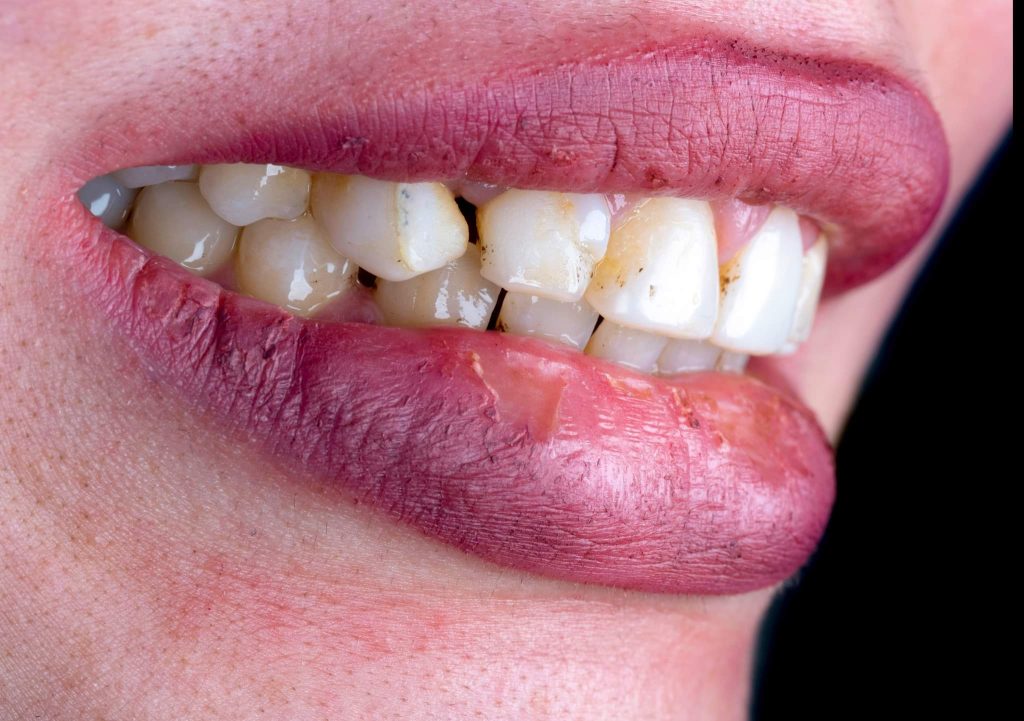

The case presented in this case report is for a 27-years-old female patient with a chief complaint of aesthetic correction for her smile. The patient was unhappy with her smile. After clinical examination, there were previous old composite veneering done poorly and incorrectly to close the multiple interdental spacing. After discussing the various treatment options (i.e., orthodontic treatment, direct, or indirect veneers), indirect ceramic veneering was selected. The step-by-step treatment protocol is presented in the images below.